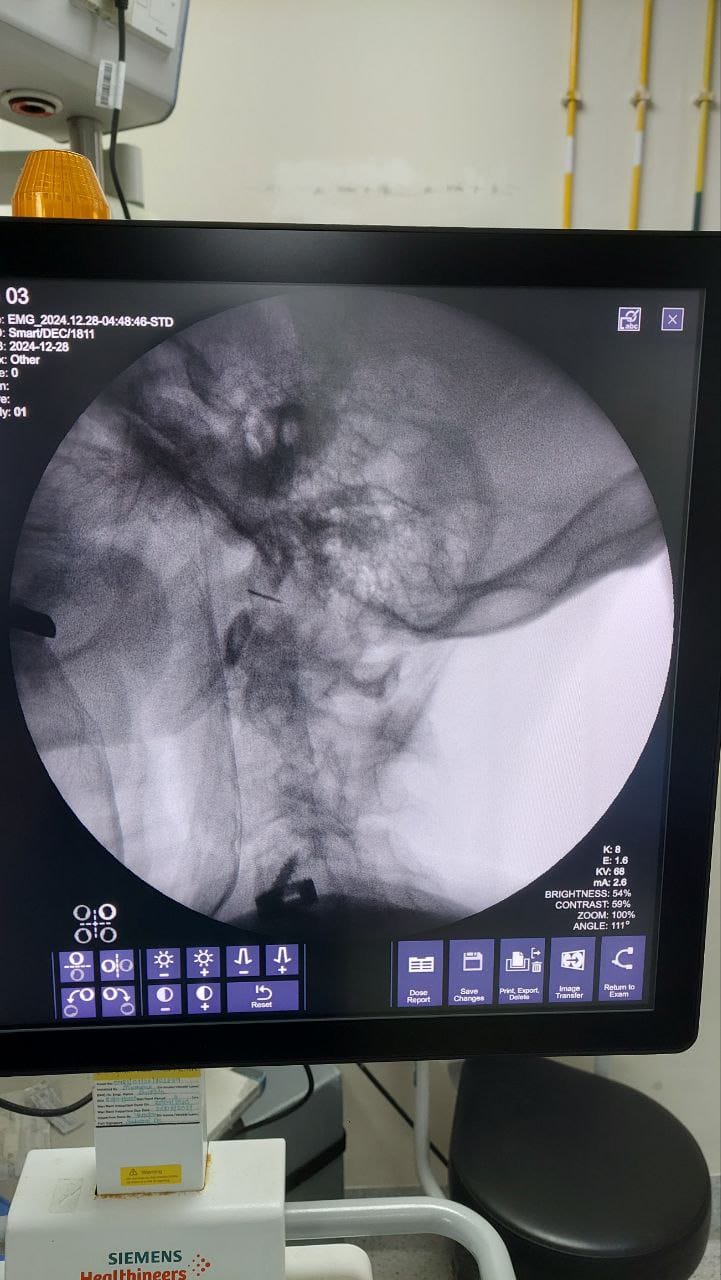

Procedures

Struggling with chronic pain? Get advanced, personalised pain management from Dr. Manish De, one of Kolkata’s leading pain specialists. From knee pain, heel pain, low back pain, frozen shoulder, migraines, cancer pain to post-TKR persistent pain—Dr. De offers safe, evidence-based treatments across multiple locations: